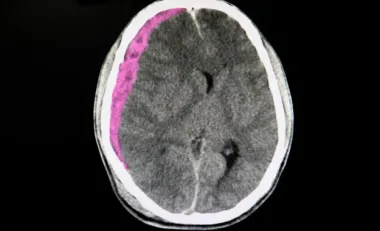

L'anosognosie survient principalement après un traumatisme ou une maladie dégénérative causant des lésions cérébrales spécifiques. Les zones les plus souvent touchées incluent le lobe pariétal droit, le lobe frontal, le thalamus et les ganglions de la base. Ces régions cérébrales jouent un rôle crucial dans la conscience de soi et l'auto-évaluation.

Les accidents vasculaires cérébraux représentent une autre cause majeure, concernant entre 10 et 18% des personnes présentant une hémiparésie après un AVC. Les traumatismes crâniens, certaines maladies infectieuses, la maladie de Parkinson ou encore la sclérose en plaques peuvent également provoquer ce trouble. Le dysfonctionnement touche particulièrement le cortex préfrontal, le cortex insulaire et le réseau du mode par défaut, ensemble de zones cérébrales impliquées dans l'introspection et la représentation de soi.